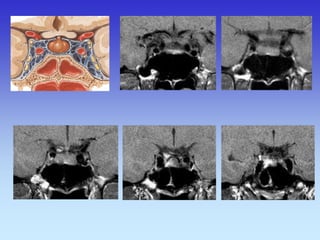

Rhombencephalon (Hindbrain) Inferior Cerebellar Peduncle

Temporal Lobe

Pons

Fourth Ventricle

Maxillary Sinus Middle Cerebellar Peduncle